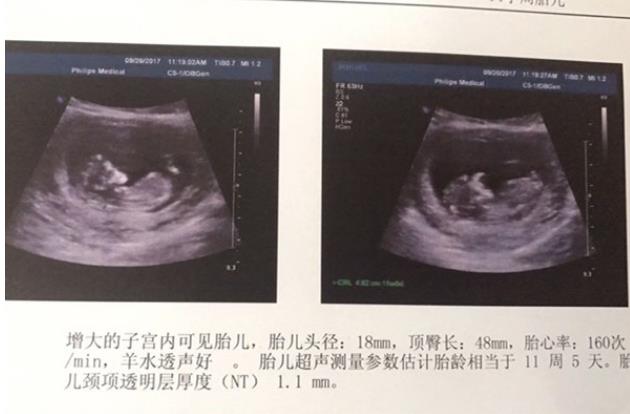

十四天官方之后,天天在家焦急等待一超快快到来。试管真的就跟过关打怪兽一样,时刻小心着。移植二十天后,我孕吐反应特别大,天天照样能吃能睡,但吃完就吐。这可能遗传我妈,我妈怀我从怀到生一直吐。估计我也差不多。

看到这张报告,我和老公超高兴!终于宝宝安营扎寨了。我所付出的都值得了。大慈大悲的观音菩萨一直保佑着我们!期待十天后的彩超,宝宝更棒!